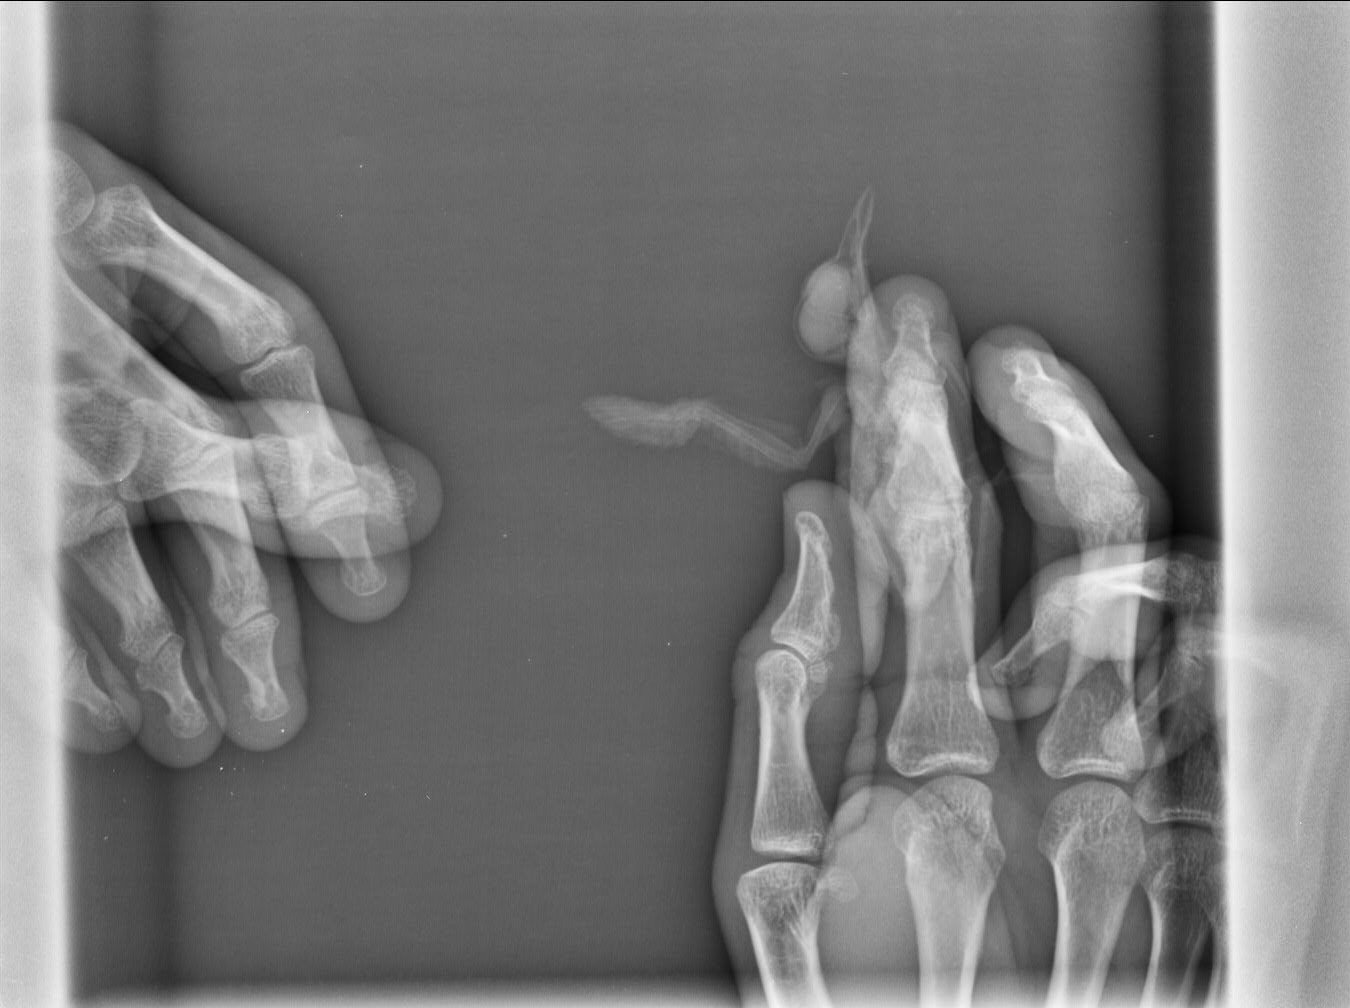

Сделали рентген, сказали что перелома нет, есть трещина и рана с гематомой.

9C63EBE9-A2F9-4B02-8EDD-882B14FD3260.jpeg